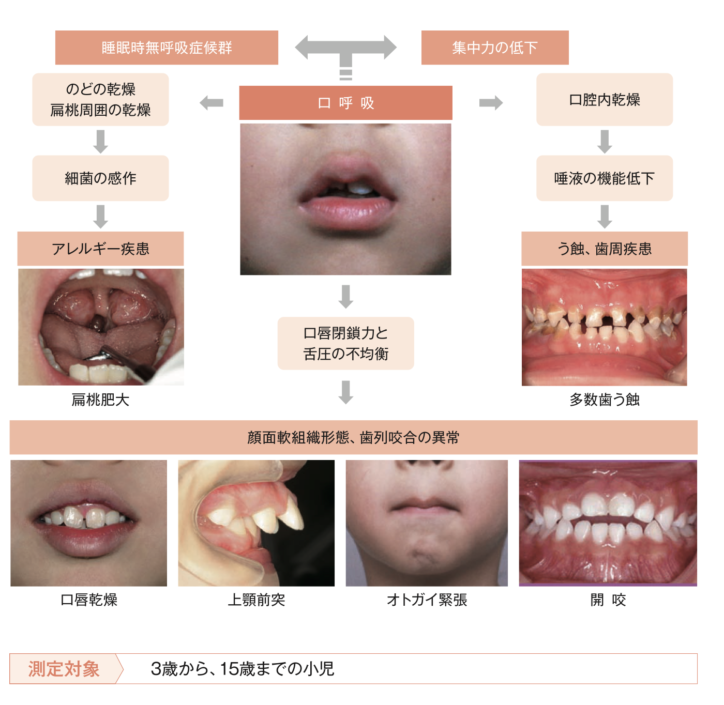

特に『お口ポカン・口呼吸』は以下のように様々な病気の重症化につながるリスクがあります。

お口を開いていることで虫歯や歯肉炎や歯並びなどのお口の問題だけでなく、アレルギーやアデノイドの肥大など様々な疾患を重症化させるリスクとなります。

つまり、お口をきちんと閉じるようにできるようになれば、口呼吸、鼻へい、気道閉塞、アレルギーなどを軽症化できる可能性もございます。

①お口ポカン・口呼吸

②くちびる・前歯が使えない

③くちびるをすぼめることができない

④舌をうまく使えない

⑤舌を置く位置が分からない

⑥正しいつばの飲み方ができない

今回は①〜③のお口を閉じる力が弱いことが原因の一つである

『口唇閉鎖力不全症』〜何もしていない時(安静時)にお口が開いている状態〜

上記のように、お口を開いていることで、虫歯や歯肉炎や歯並びなどのお口の問題だけでなく、アレルギーやアデノイドの肥大など様々な疾患を重症化させるリスクとなります。

つまり、お口をきちんと閉じるようにできるようになれば、口呼吸、鼻へい、気道閉塞、アレルギーなどを軽症化できる可能性もございます。